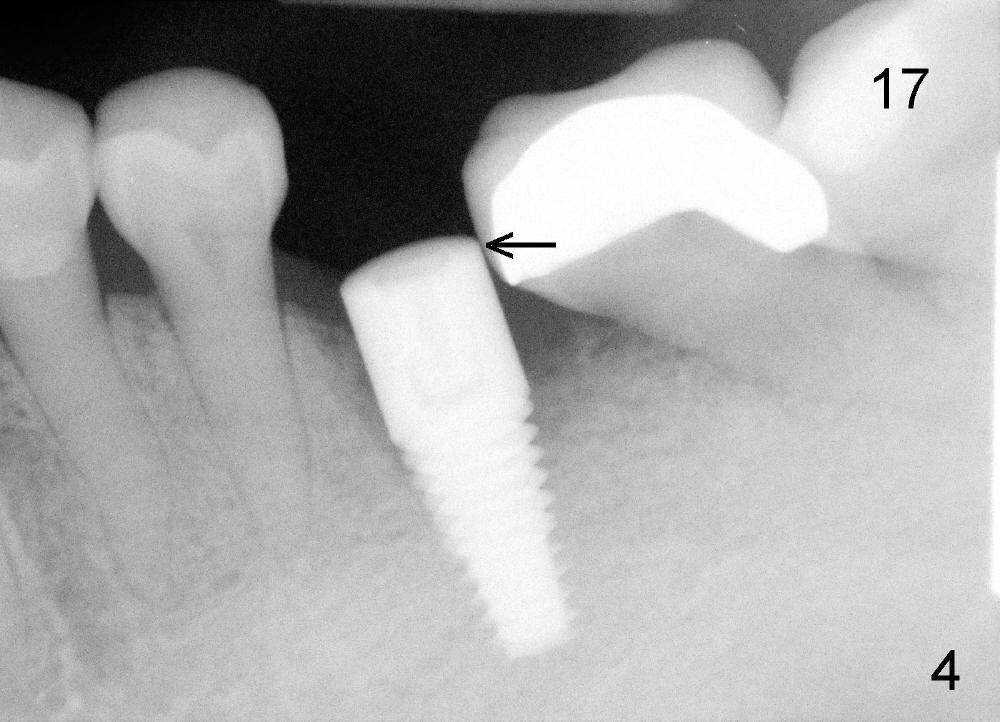

A 42-year-old man has poor dentition with missing multiple teeth. He was a smoker. After smoke cessation, two implants are placed at the sites of #3 (6x17mm) and 19 (5x14mm) (Fig.1,2). It does not sound great to place #3 implant close to a potential infection site (#5, Fig.1). But the latter is asymptomatic. Four months post #3 implantation, he returns with pain in the upper right sextant (Fig.3). The tooth #18 appears to shift mesially (Fig.4). To place a crown over #19 implant, the mesial surface of the crown of #18 has to be trimmed. What cannot be done associated with #18 shifting is food impaction between #17 and 18 (Fig.8). Clinical exam reveals crack of the tooth #4. Immediate implant is planned. Is it too close to the infection site?